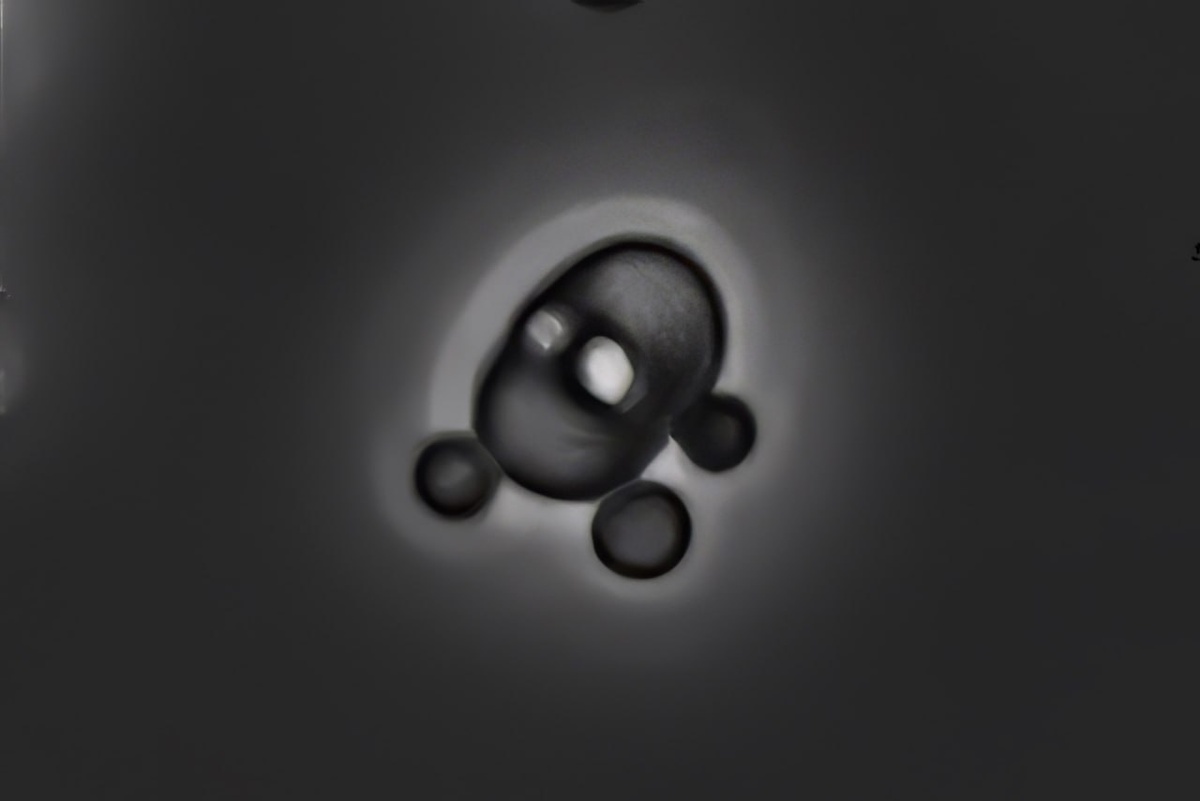

Акантоцит в осадке мочи

Фазово-контрастная микроскопия, темнопольная микроскопия. #осадокмочи #моча

Акантоцит в осадке мочи. Фазово-контрастная микроскопия, темнопольная микроскопия.